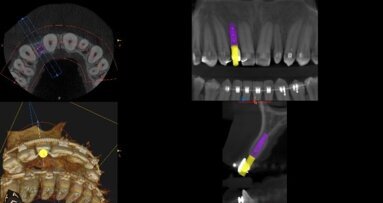

25-letnia pacjentka, ogólnie zdrowa, niepaląca zgłosiła się w celu uzupełnienia braku zębów 24-26. Zaplanowano podniesienie dna zatoki szczękowej metodą otwartą z jednoczesnym wprowadzeniem 2 implantów, a po okresie gojenia most 24-26 (Ryc. 18 i 19).

Po odpreparowaniu płata przygotowano łoże implantu w miejscu 24 i wprowadzono implant BEGO Semados S3, 25L 11,5. Następnie z użyciem SLA Kit wykonano okienko w ścianie zatoki. Podczas preparacji błony śluzowej zatoki doszło do niewielkiej perforacji, którą zaopatrzono błoną kolagenową BEGO Membrane. Do zatoki wprowadzono BEGO Oss, przygotowano łoże implantu 26 i wprowadzono implant BEGO Semados S3, 75L 11,5. Jako śrubę zmykającą zastosowano śrubę typu Engelke, która uniemożliwia przemieszczenie implantu w kierunku światła zatoki szczękowej. Wykonano boczną augmentację w okolicy 24 materiałem BEGO Oss oraz całość pokryto błoną kolagenową BEGO Membrane. Założono szwy nieresorbowalne (Ryc. 20-27).

Po 7-miesięcznym okresie gojenia implanty odsłonięto i przystąpiono do wykonania ostatecznej pracy protetycznej – mostu cyrkonowego na łączniku cyrkonowym i tytanowym (Ryc. 28-31).